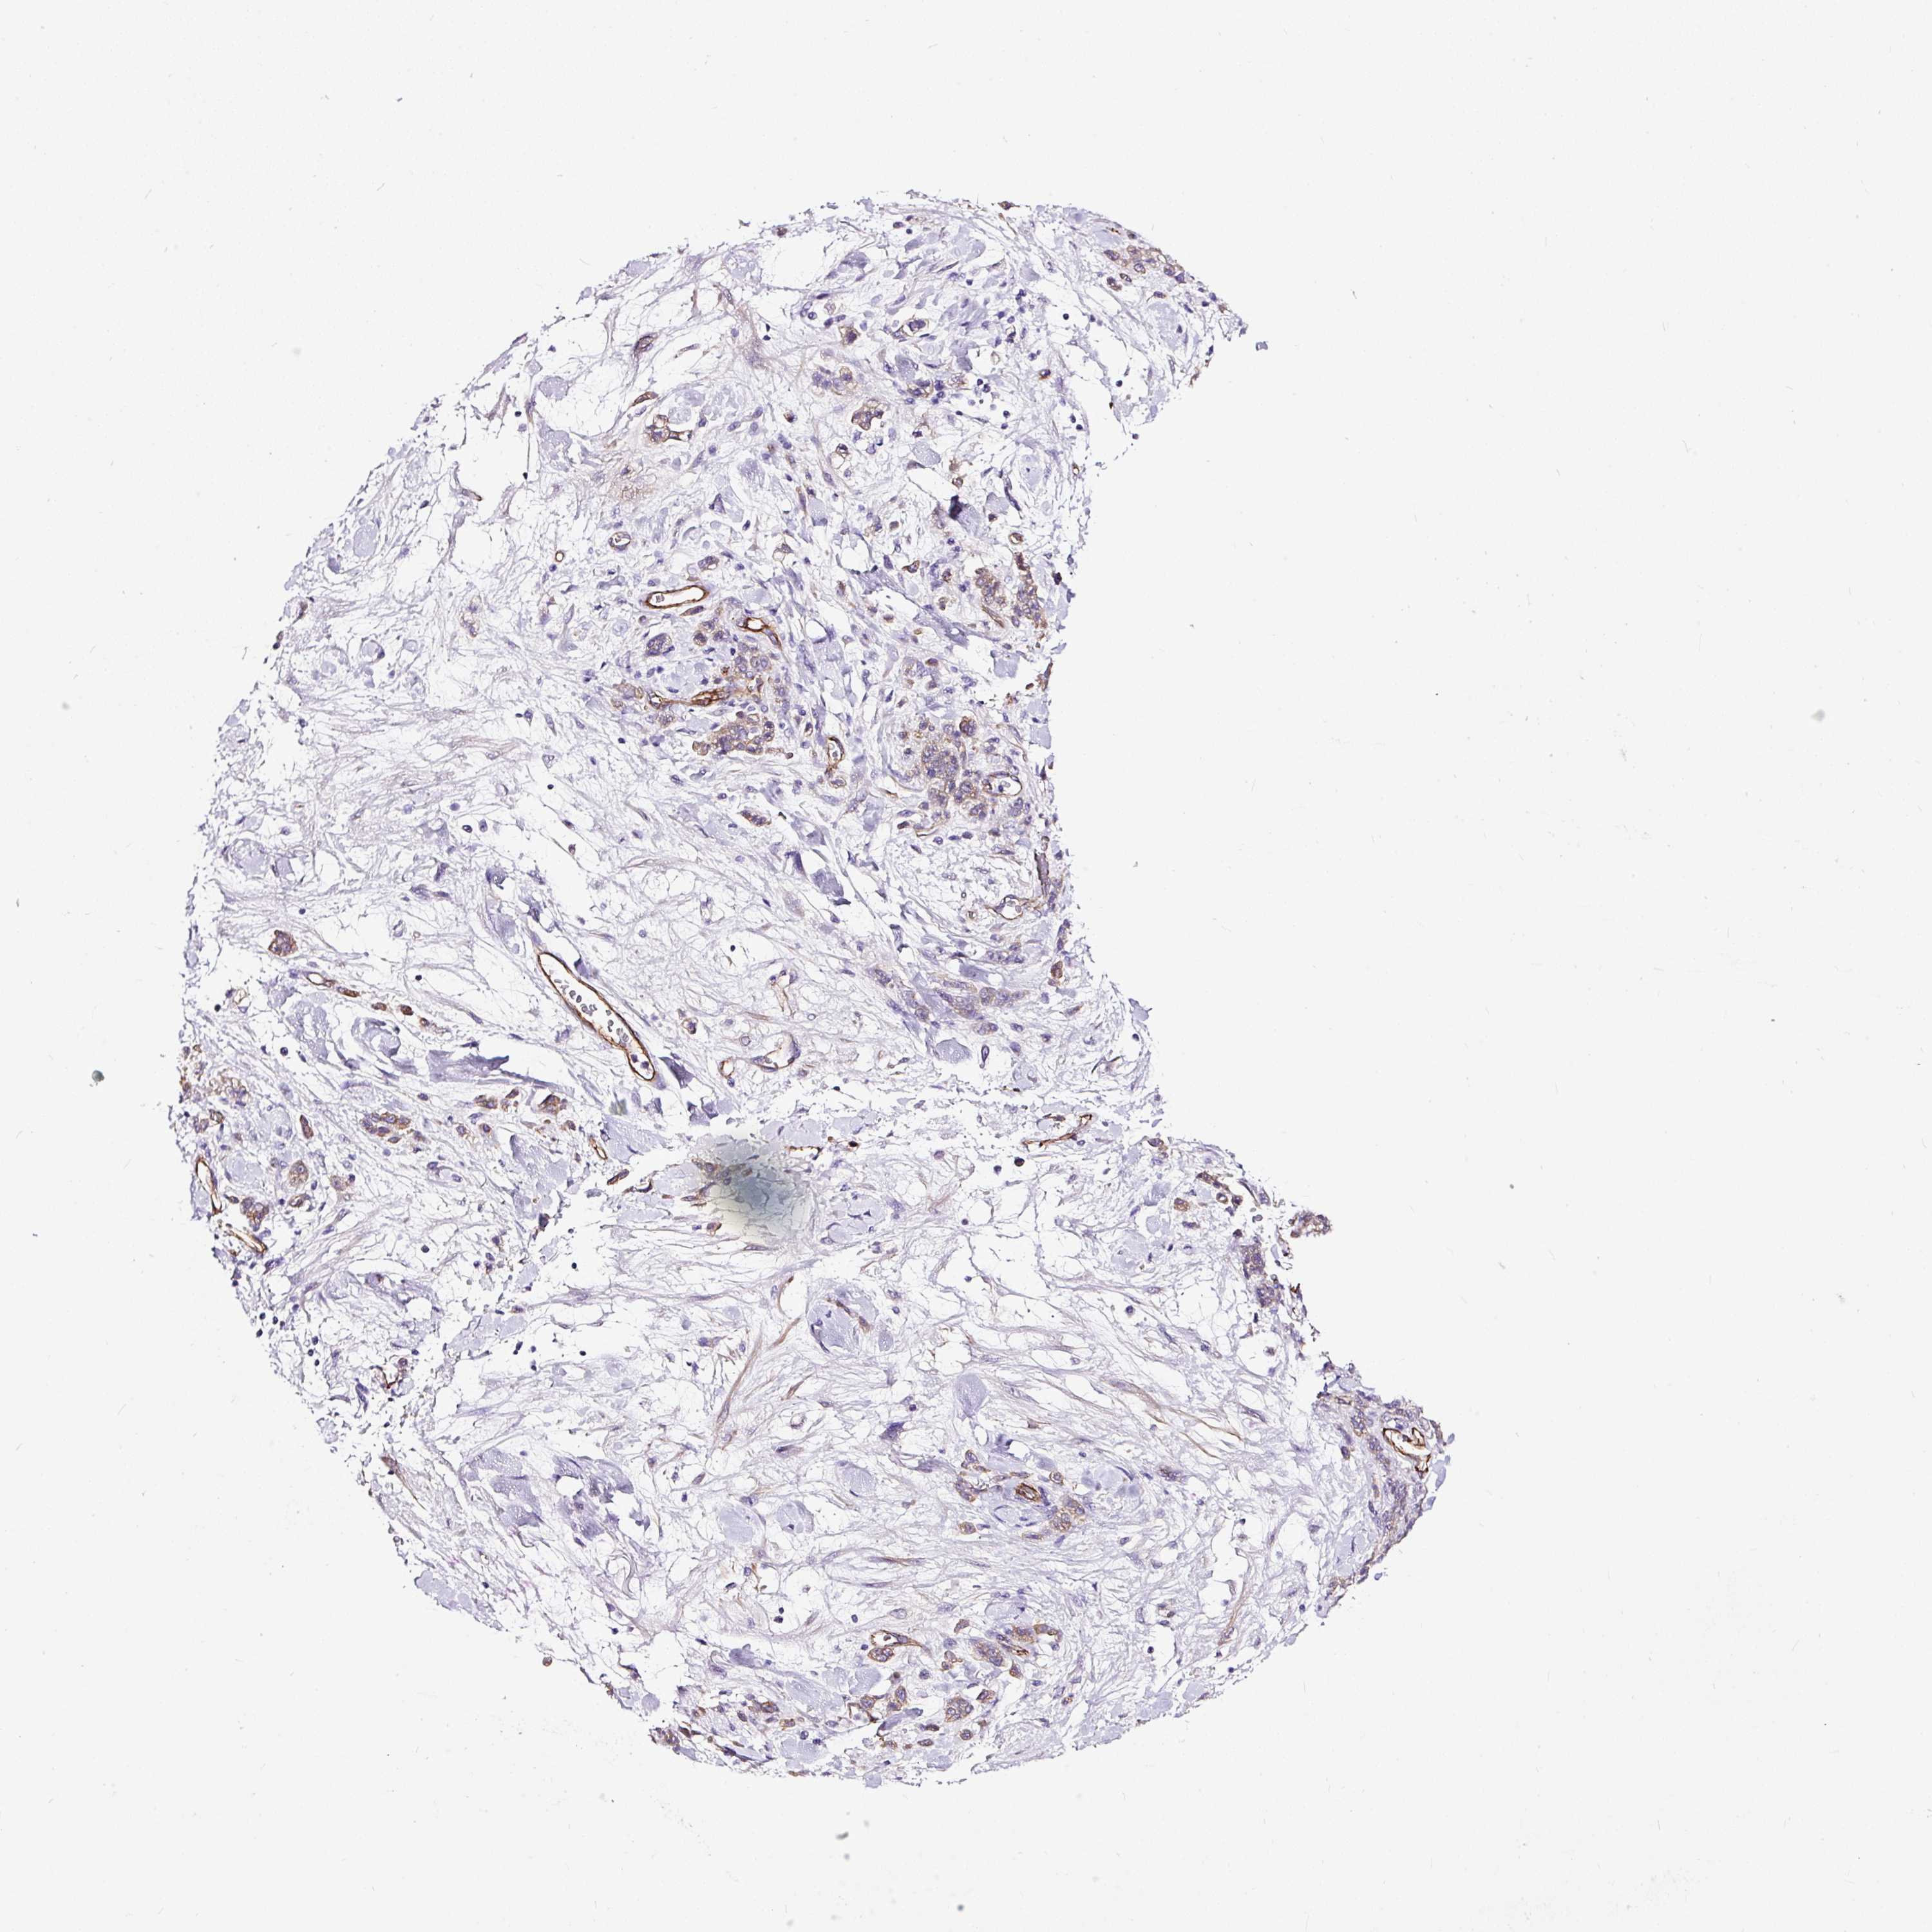

STOMACH CANCER - Protein expressioni

A mouse-over function shows sample information and annotation data. Click on an image to view it in a full screen mode. Samples can be filtered based on level of antibody staining by selecting one or several of the following categories: high, medium, low and not detected. The assay and annotation is described here.

Note that samples used for immunohistochemistry by the Human Protein Atlas do not correspond to samples in the TCGA dataset.

Antibody stainingi

Antibody staining in the annotated cell types in the current human tissue is reported as not detected, low, medium, or high, based on conventional immunohistochemistry profiling in selected tissues. This score is based on the combination of the staining intensity and fraction of stained cells.

Each image is clickable and will lead to virtual microscopy that enables deeper exploration of all samples and also displays staining intensity scores, fraction scores and subcellular localization as well as patient and tissue information for each sample.

Antibody HPA055743

Staining

High

Medium

Low

Not detected

Intensity

Strong

Moderate

Weak

Negative

Quantity

>75%

75%-25%

<25%

None

Location

Nuclear

Cytoplasmic/membranous

Cytoplasmic/membranous,nuclear

Adenocarcinoma, NOS